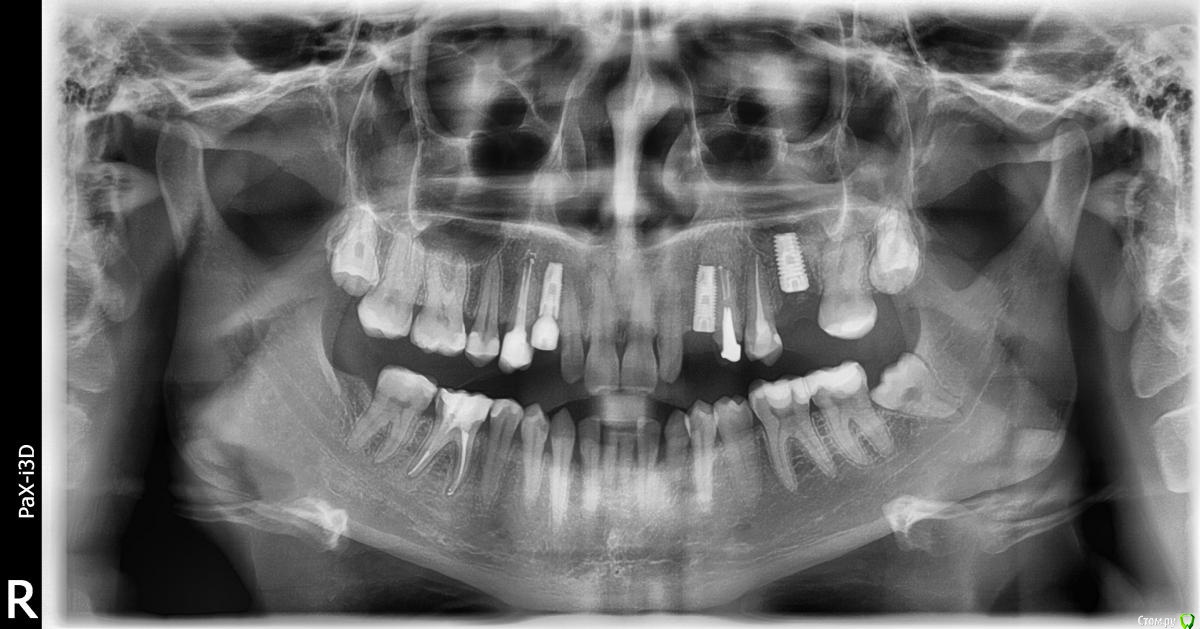

fifa888.dexo Опубликовано 12 июля, 2015 Поделиться Опубликовано 12 июля, 2015 Здравствуйте.2.07.2015 мне была проведена операция по установке трех имплантов альфа био и открытому синус-лифтингу. Т.е. два клыка сверху(на их местах раньше были молочные зубы без зачатков коренных), и верхней 6 слева.Шестерка была удалена давно и потребовался синус-лифтинг,врач поставил имплант туда сразу. После операции была конечно сильная боль,пила найз, антибиотик рулид,полоскала хлоргексидином, капала в нос виброцил и вообще соблюдала строжайше все рекомендации врача.3.07.2015 боль была меньше начал появляться отек,но все как предупреждали врачи т.е. в пределах нормы,съездила в клинику меня посмотрели все нормально.4.07.2015 обезбаливающее пила только к вечеру, днем было нормально только стала болеть голова и беспокоило чувство перекатывания в пазухе при наклоне головы,я думала из-за отека.5.07. места имплантации не беспокоили практически, поехала к врачу сказала про перекатывания в пазухе и был немного белый налет на деснах он сказал что это все нормально.К вечеру опять разболелась голова таблетка найза все разрешила.6.07 стал сходить отек немного пожелтела скула был последний день приема антибиотика,ничего не беспокоило только чувство перекатывания при наклоне головы и немного побаливала голова. Обезбаливающие не пила.7.07. в обед стало беспокоить место синус лифтинга началась боль которая к вечеру перешла в пульсирующую. Выпила обезбаливающее,чаще делала ванночки с хлоргексидином.8.07. Проснулась от дергающей боли в месте синуса и вообще всей пазухи,языком нащупала между десной где проводился синус лифтинг и щекой горячее уплотнение,щека тоже была горячее чем вторая,но температуры не было, поехала срочно к врачу!!!Врач посмотрел пощупал сказал что шишка в норме но отправил на снимок,позвали к себе после снимка сказали что немного осыпалась искуственная кость (био осс), спросили не чихала ли я,говорю что нет. Говорю что делать сказали подождать в коридоре.Врач бегал мимо меня кого то искал,потом с мужчиной удалился в кабинет,через пять мин позвали меня.Мужчина оказался лор сказал что они мне предлагают сделать прокол так как в пазухе у меня воспаление и по другому его не снять.Я в шоке.Мой врач кивает. Пазухи смотрели на кт перед операцией все было нормально и вообще у меня никогда не было гайморита!!!Я согласилась.Прокололи, помыли 2 раза и третий раз с антибиотиком.Назначили тизин и цефтриаксон колоть 7 дней по 2 раза в день.И все!Врач сказал на снятие швов 16.07. Вечером начлась адская боль в щеке все дергало шишка вздулась еще больше, отек сошел почти,но сама пазуха была намного выше второй.Я не могла уснуть до двух ночи обезбаливающее почти не помогало. С утра стало гораздо легче был горький привкус во рту,шишка стала меньше,а по задней стенке горла текла ручейком кровь потом перестала и начали отходить сгустки гноя и слизи через нос и через носоглотку(я не сморкалась тизин как то прогонял видимо)при наклоне все вытекало.А самое главное чувство перекатывания в пазухе полностью ушло!!!Сегодня 12.07 шишка сошла еще вчера,но пазуха до конца так и не опустилась я чувствую что там еще что-то есть, не дергает,не болит, гной больше не выходит..только при нажатии на пятерку рядом с место синуса немного больно хотя она депульпирована. У меня есть панорамный снимок за сегодня и КТ перед проколом. Скрины с КТ делать не умею.Может на панорамке что то будет видно??Меня интересует вот что - разве может что-то прижиться после такого воспаления,может надо все вынимать???И кость осыпалась я видела на кт у них что оголен немного верх импланта, но врач сказал ничего страшного.Пазуху смотреть я пойду к другому лору,наверно еще отмывать надо будет...И посмотрите пожалуйста имплант справа(3),мне кажеться там задели корень соседнего зуба.Я вообще не понимаю что мне делать,понятно что это все не нормально,а врач говорит ничего все будет хорошо,настройтесь на позитивный лад.И вообще откуда это воспаление от осыпавшейся кости или наоборот кость осыпалась от хлынувшего гноя,или что вообще???Очень надеюсь на ваши хоть какие нибудь разъяснения.Заранее благодарю))) Ссылка на комментарий

Bier Опубликовано 13 июля, 2015 Поделиться Опубликовано 13 июля, 2015 справа (на орто слева) еще недосажен формирователь десны. Ссылка на комментарий

fifa888.dexo Опубликовано 13 июля, 2015 Автор Поделиться Опубликовано 13 июля, 2015 (изменено) 1. Может ли био осс сохранить свою функцию после воспаления(или что это было??),т.е вынимать или может еще может прижиться?Я подозреваю что идет вялотекущий процесс который подснялся антибиотиком и боюсь за свою кость и соседние зубы.2. Если смотреть по кт задел ли имплант слева (по снимку справа) корень соседнего зуба?3. Если даже там больше нет воспаления кость то осыпалась,насколько это критично?4. Рядом с имплантом где недокручен формирователь зуб №2 - при надкусывании чувство онемения,это из-за того что имплант близко?Чем это опасно?Вот вроде и все.Очень жду вашего мнения. Изменено 13 июля, 2015 пользователем fifa888.dexo Ссылка на комментарий